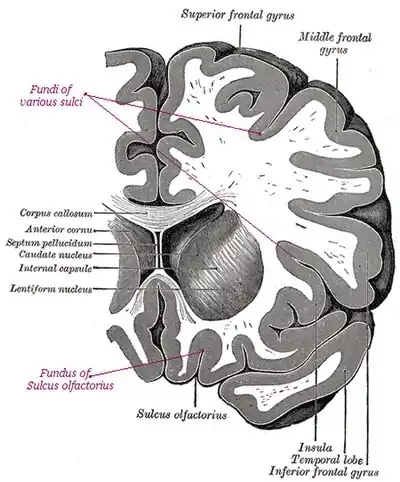

Fundi, sulci, and gyri in a section across a human brain

Fundi, sulci, and gyri in a section across a human brain

The deepest part of a sulcus, such as the sulci in the human cerebral cortex.[1]